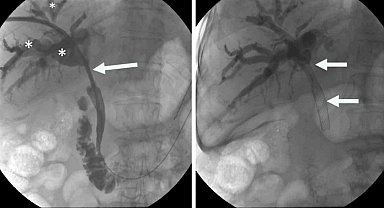

Hibrit yaklaşımla, zorlu safra yolu tedavilerinde yeni dönem